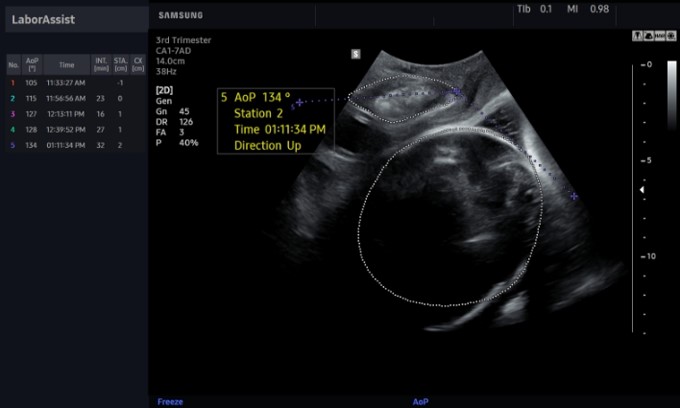

Функция LaborAssist™ помогает оценить положение тела и головы ребенка, чтобы врач мог контролировать движение плода во время родов. Кроме того, всегда существует риск замедления родового процесса. Точная информация о ходе родов в режиме реального времени помогает врачам определить лучший способ родоразрешения и позволяет сократить количество операций методом кесарева сечения.

«LaborAssist™ автоматически измеряет угол положения плода, а также предоставляет врачу информацию о состоянии и расположении головы будущего ребенка. На экране видны изменения положения головы – это помогает объяснить пациентке и ее родственникам, как протекает процесс родов. Мы считаем, что эта технология будет полезна в оценке прогресса родов и выборе способа родоразрешения», – прокомментировал Мин Чжон О (Min Jeong Oh), доктор медицинских наук, профессор отделения акушерства и гинекологии больницы Гуро, Корейского университета в Сеуле.